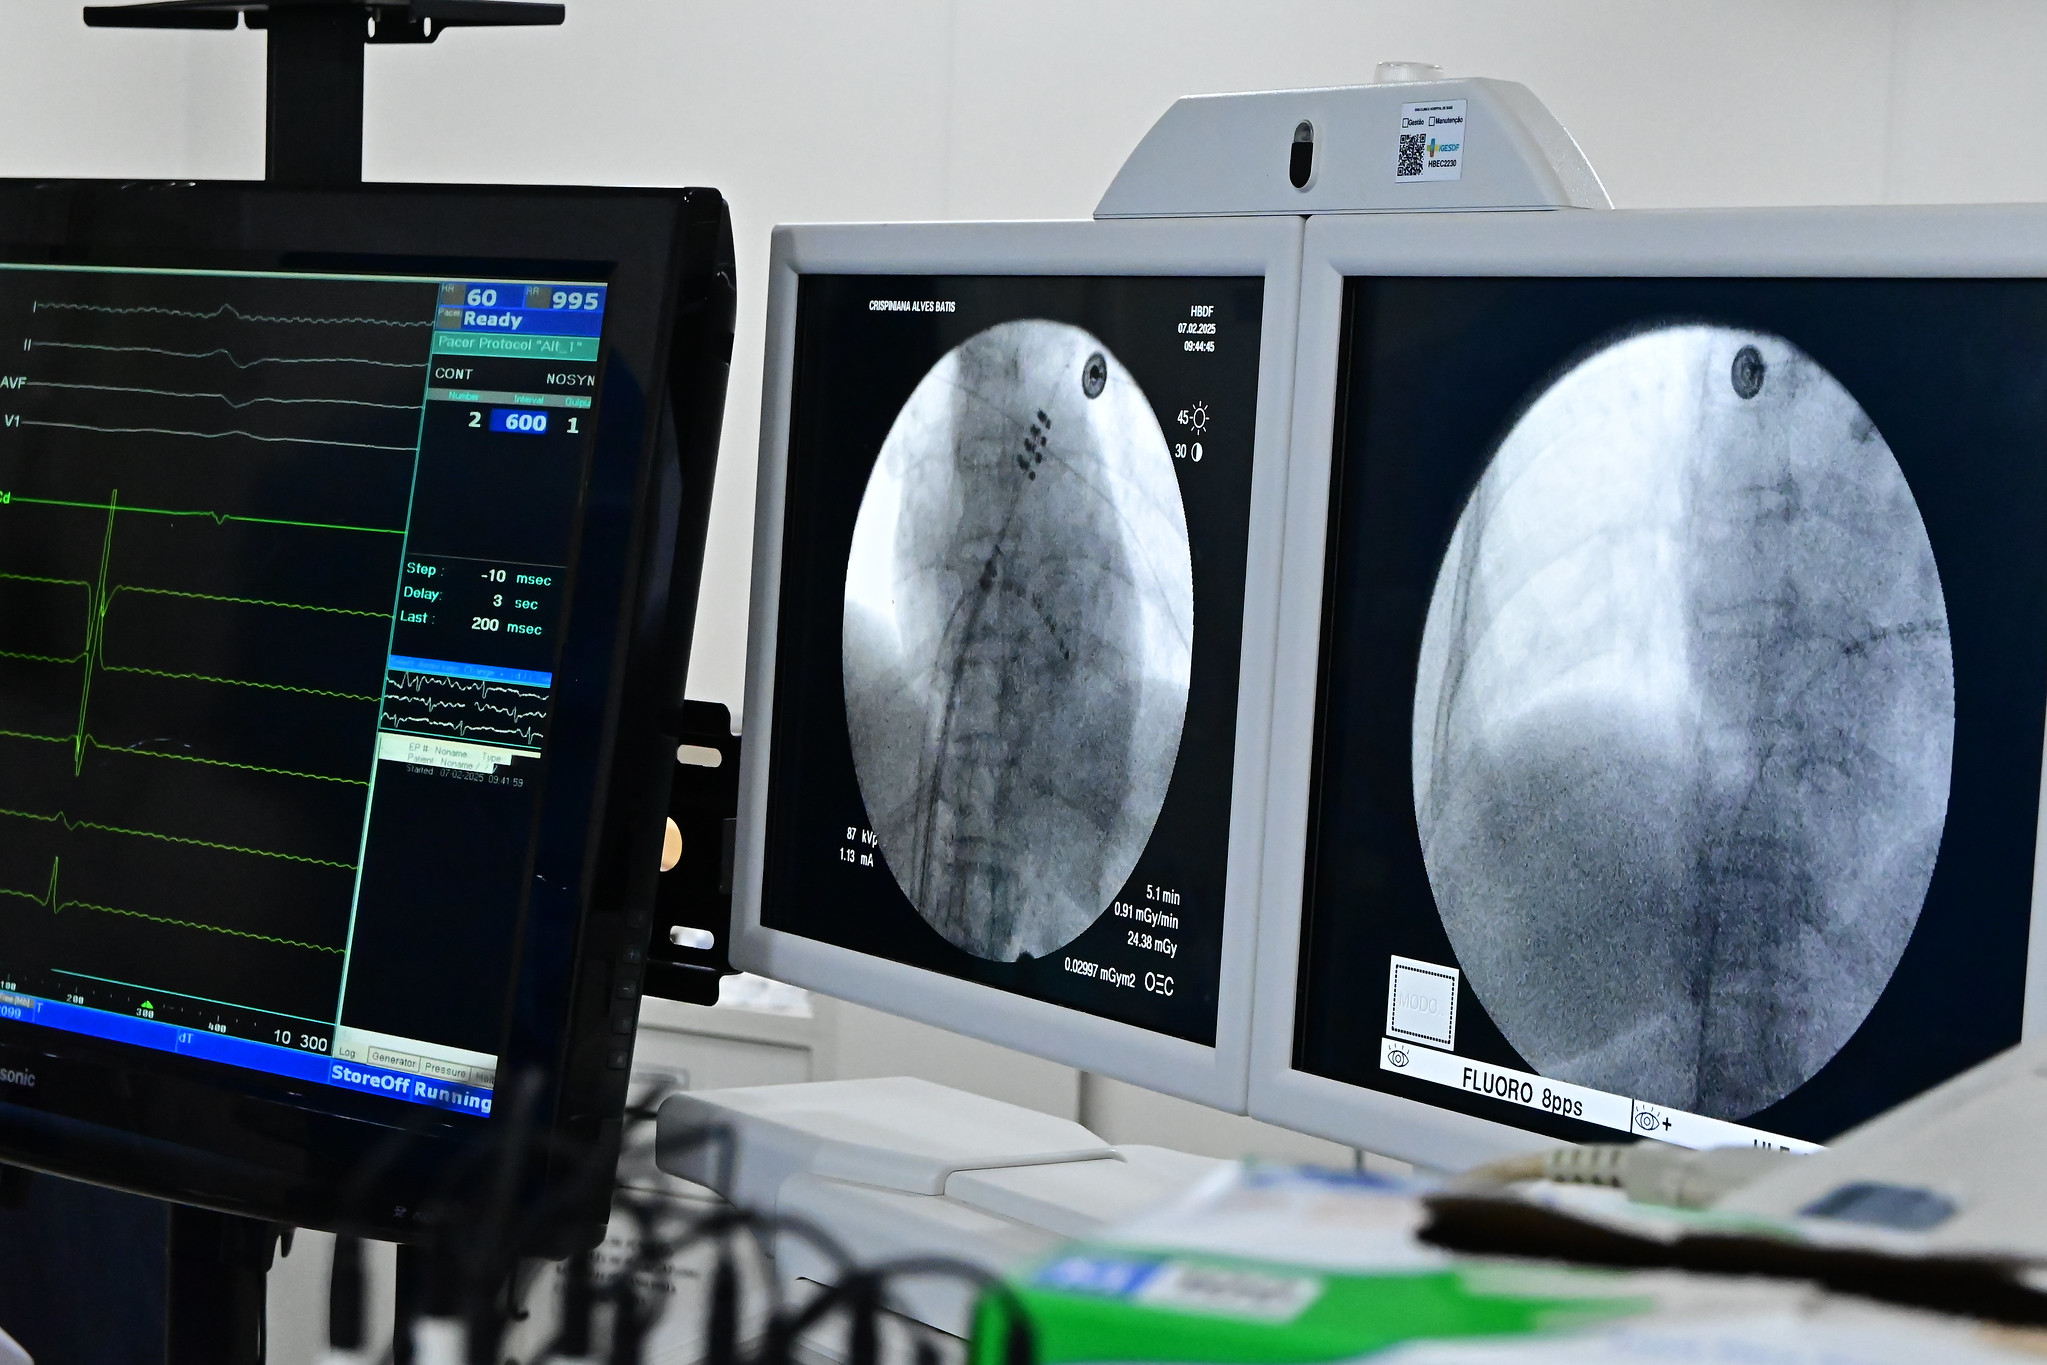

Na última sexta-feira (7), o Hospital de Base do DF (HBDF) tornou-se a primeira unidade de saúde 100% SUS a realizar um procedimento inovador para o tratamento de arritmias cardíacas com a ablação e aplicação de pulso de elétrons (PFA). Essa técnica minimamente invasiva não exige centro cirúrgico, UTI, anestesia geral nem internação prolongada, representando um avanço no tratamento da doença dentro da rede pública de saúde.

Por não exigir centro cirúrgico, UTI, anestesia geral ou internações longas, a PFA proporciona mais precisão aos médicos e mais conforto aos pacientes | Fotos: Alberto Ruy/ IgesDF

A eletrofisiologista invasiva Carla Septimio Margalho, supervisora do Programa de Residência em Eletrofisiologia Clínica e Invasiva do Hospital de Base, explica que a técnica é revolucionária: “A PFA utiliza uma tecnologia nova, desenvolvida recentemente, que permite a realização da ablação com mais segurança e eficiência. O procedimento, chamado ablação de fibrilação atrial com aplicação de pulso de elétrons, é um marco no tratamento da arritmia e já tem mostrado resultados promissores”.

Com a nova técnica, uma operação que poderia durar até 10 horas é resolvida em cerca de 55 minutos

“O que antes levava oito horas a dez horas e exigia UTI, agora pode ser realizado em cerca de 55 minutos. O paciente pode ser encaminhado à enfermaria e recebe alta em poucos dias, o que reduz riscos, otimiza o atendimento e diminui custos”, explica o cardiologista Henrique Cesar.